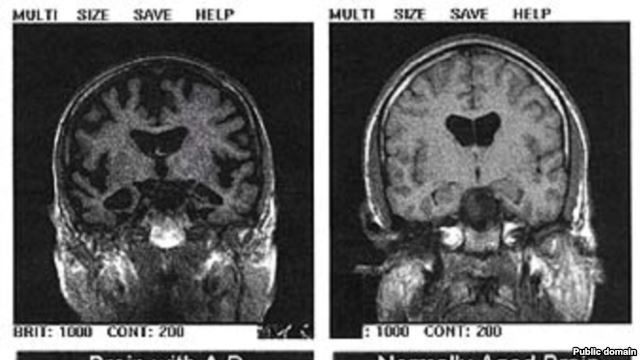

Alzheimerova bolest ima vrlo dugu predkliničku fazu i počinje godinama prije nego što pacijenti imaju bilo kakve simptome gubitka pamćenja. Ona utječe na oštećenja u mozgu puno prije dijagnosticiranja pa brojna istraživanja novih lijekova propadnu zbog toga što je mozak pacijenata kojima se daju lijekovi već jako zahvaćen bolešću.

Jedna od metoda je pokušati detektirati beta amiloide koji se razvijaju tijekom bolesti. Otprije je poznato da se mogu otkriti skeniranjem mozga, no riječ je o skupim i nepraktičnim metodama, kaže profesor Colin Masters sa sveučilišta u Melbourneu.